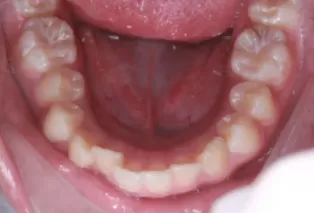

Photos intra-orales